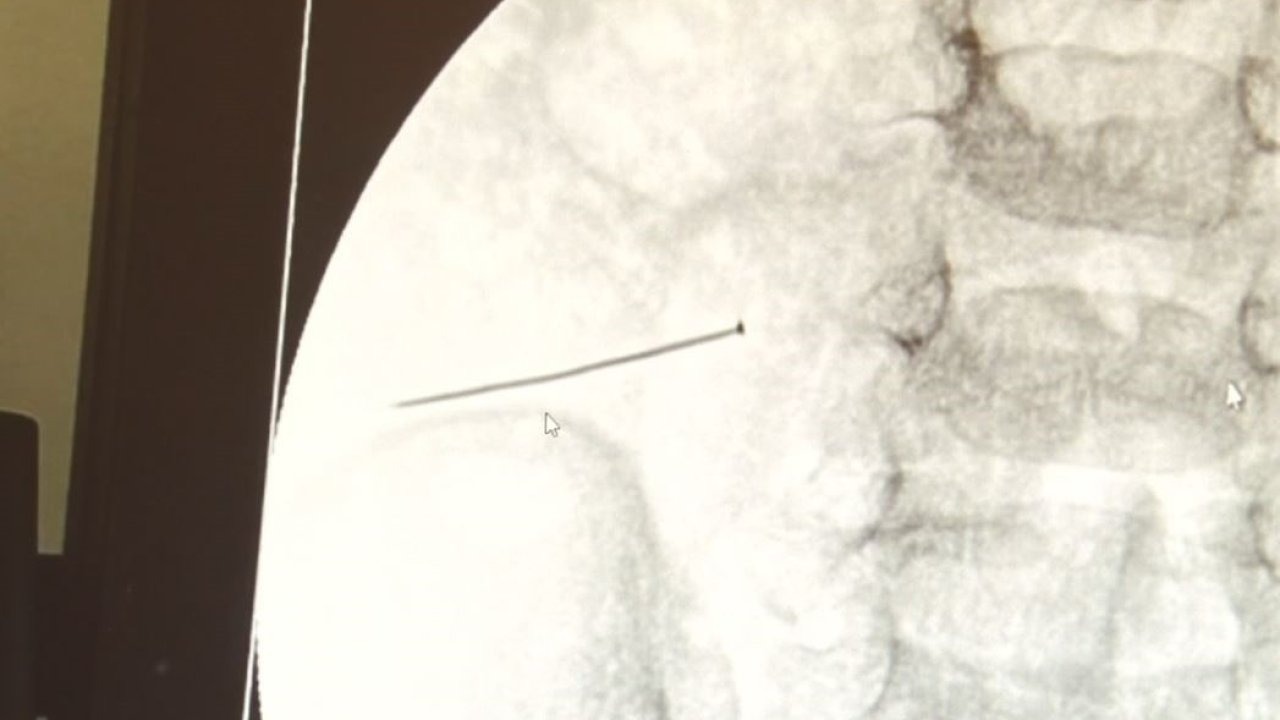

Öte yandan, yaklaşık 3 santimlik toplu iğne filme yansıyan görüntüsüyle gözler önüne serildi.

Çocuklarda yabancı cisim yutulmasına yönelik konuşan ve hastasına ilişkin bilgi veren Doç. Dr. Sefa Sağ, "Soluk borusuna kaçması durumunda çocuğun Allah göstermesin ölümüyle veya ömür boyunca yatağa bağımlı kalmasıyla neticelenebilecek sonuçlar doğurabiliyor. Yutulması durumunda da gastrointestinal sistemin herhangi bir yerine takılmadığı müddetçe ekseriyâ yabancı cisimlerin dışarıya çıkmasını bekliyoruz. Yabancı cisim yutulmasını 2 grupta inceleyebiliriz. Sıvı ve katı cisimler olarak sıvı; evde kullanılan kimyasal temizlik malzemelerinin yutulması çok ciddi problemler oluşturabilmekte. Ağızda, yemek borusunda ve midede yanıklar meydana getirebilmekte. Uzun dönemde çocukların hayat kalitesini oldukça etkileyen sonuçlar doğurabilmekte. Katı cisimlerden de ekseriyâ kendiliğinden çıkmasını bekleriz ancak böyle delici, kesici aletlerin yutulmasında ise herhangi bir bağırsağın veya gastrointestinal sistemin bir parçasında delinmeler meydana getirebiliyor. Bu çocuğumuzda da aynen böyle bir hadise meydana gelmişti. Sanırım 1 gün önce ailenin yuttuğunu tahmin ettiği bir yabancı cisim; toplu iğne. Ertesi gün bağırsakta delinmeyle sonuçlanmış ve çocukta da ciddi semptomlar meydana getirmişti. Bu şekilde hasta bize başvurdu. Tetkikler sonucunda yabancı cismi tespit ettik, semptomları ve bulgularına göre de çocuğu ameliyata aldık. Yaklaşık 3 santim boyunda bir toplu iğnenin ince bağırsağı deldiğini, ince bağırsaktaki içeriğin de karın içerisine dolduğunu gördük. Ameliyatı başarılı bir şekilde tamamladık, yaklaşık 1 saat süren bir ameliyattı" dedi.